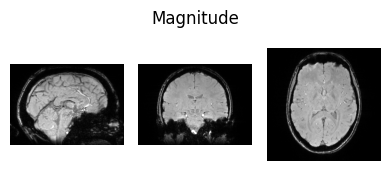

Inspect input data#

Here we define a function we will use to visualise NIfTI images so we can view some of the input data:

show_nii(glob("bids/sub-*/ses-*/anat/*mag*T2starw*nii*")[0], title="Magnitude", vmax=500)

show_nii(glob("bids/sub-*/ses-*/anat/*phase*T2starw*nii*")[0], title="Phase")

show_nii(glob("bids/sub-*/ses-*/anat/*T1w*nii*")[0], title="T1-weighted")